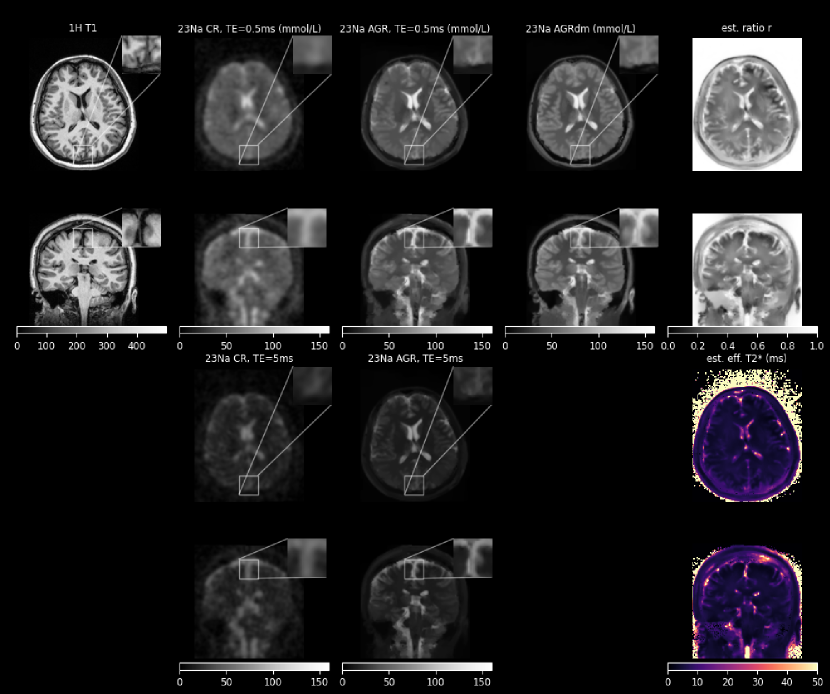

Figures 5, 6, and 7 show the conventional (CR) and anatomically-guided sodium reconstruction without and with signal decay estimation and modeling (AGR and AGRdm) for the three dual echo sodium acquisitions. In all three cases, the boundaries between GM, WM and CSF are much better defined in the anatomically-guided reconstructions, leading, e.g., to a clearer separation between the sodium concentration in GM and WM and also between the CSF in the sulci and cortical gray matter. Moreover, within WM and GM, both AGRs are less noisy compared to the conventional reconstruction. The estimated decay ratio image (the exponential transformation of the effective estimated monoexponential T2superscriptsubscript𝑇2T_{2}^{*} time) clearly shows the relatively slow signal decay in CSF (r𝑟r close to 1) and faster decay in GM and WM. Figure 8 shows a comparison of the sodium concentration of GM and WM in the cortical region obtained with the three reconstructions in all three cases. The higher cortical GM to WM contrast of AGRdm that can be also clearly seen in Fig. 5 is also confirmed in the plot of cortical GM to WM sodium concentration displayed in the right of Fig. 8. Morever, AGR and AGRdm also lead to higher GM to brainstem sodium concentration ratios which are more in line with the ratios of healthy controls reported in [7] where partial volume correction was applied post reconstruction in image space.

Refer to caption

Figure 7: Same as Fig. 5 for the second healthy control (42yr, F).